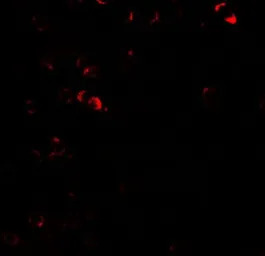

IHC-P analysis of human lymph node tissue using GTX31589 E2F3 antibody.

Working concentration : 5 μg/ml

Working concentration : 20 μg/ml